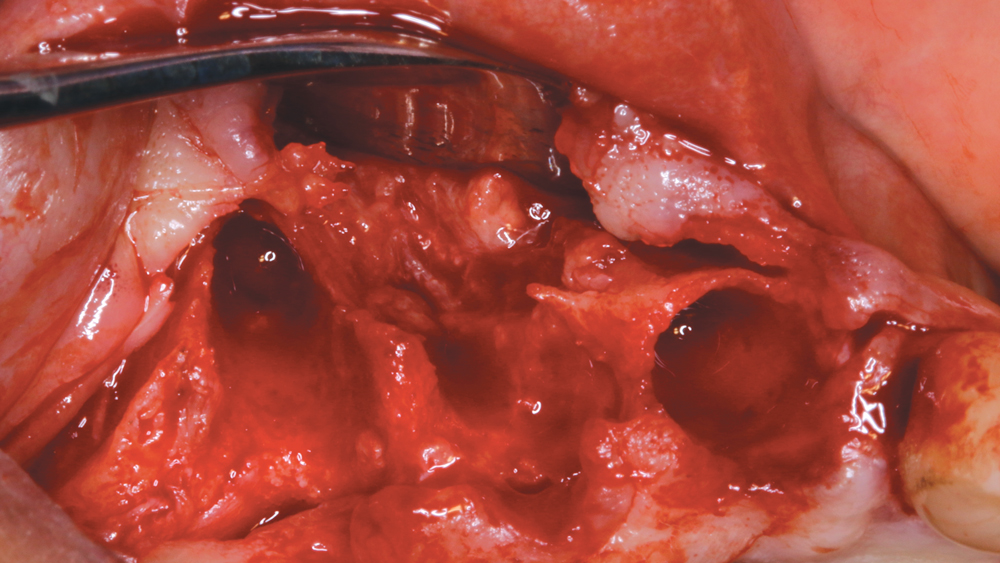

After removing the untreatable teeth, I placed five Hahn Tapered Implants into the extraction sockets, grafted the area with Newport Biologics™ Mineralized Cortico/Cancellous Allograft Blend (Glidewell Direct) mixed with harvested autograft from the osteotomy sites, and used a Newport Biologics Resorbable Collagen Membrane 3-4 (Glidewell Direct) as a barrier against epithelial downgrowth during the healing and remodeling phase.